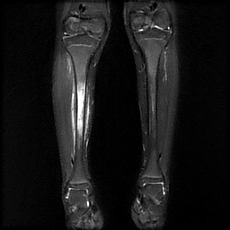

Viêm xương tủy mạn tính (Chronic osteomyelitis)

16/03/2026